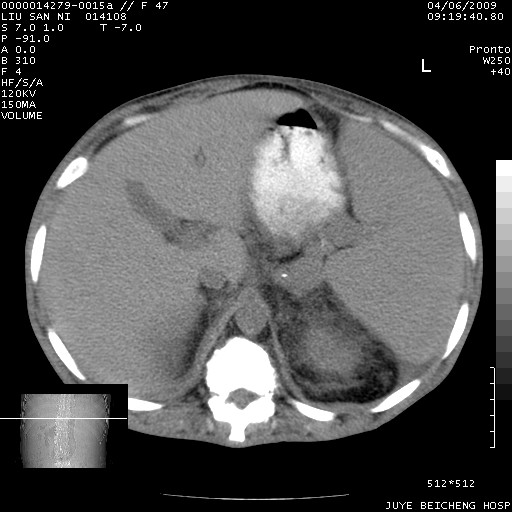

以下是引用前行在2009-4-7 10:31:00的发言:[br]肝脾肿大;双肾增大,双肾盂少量积水可能,肾膜膜增厚,肾周间隙增宽,并见桥间隔,提示结缔组系统疾病、系统性红瘢狼疮肾可能性大。继发右侧胸腔、心包、腹腔积液。

以下是引用深泽交通医院在2009-4-7 11:21:00的发言:[br]双侧肾周密度增高,见条索影,右肾实质见点片状低密度区,考虑弥漫肾炎【自身免疫性?】;;肾性水肿征